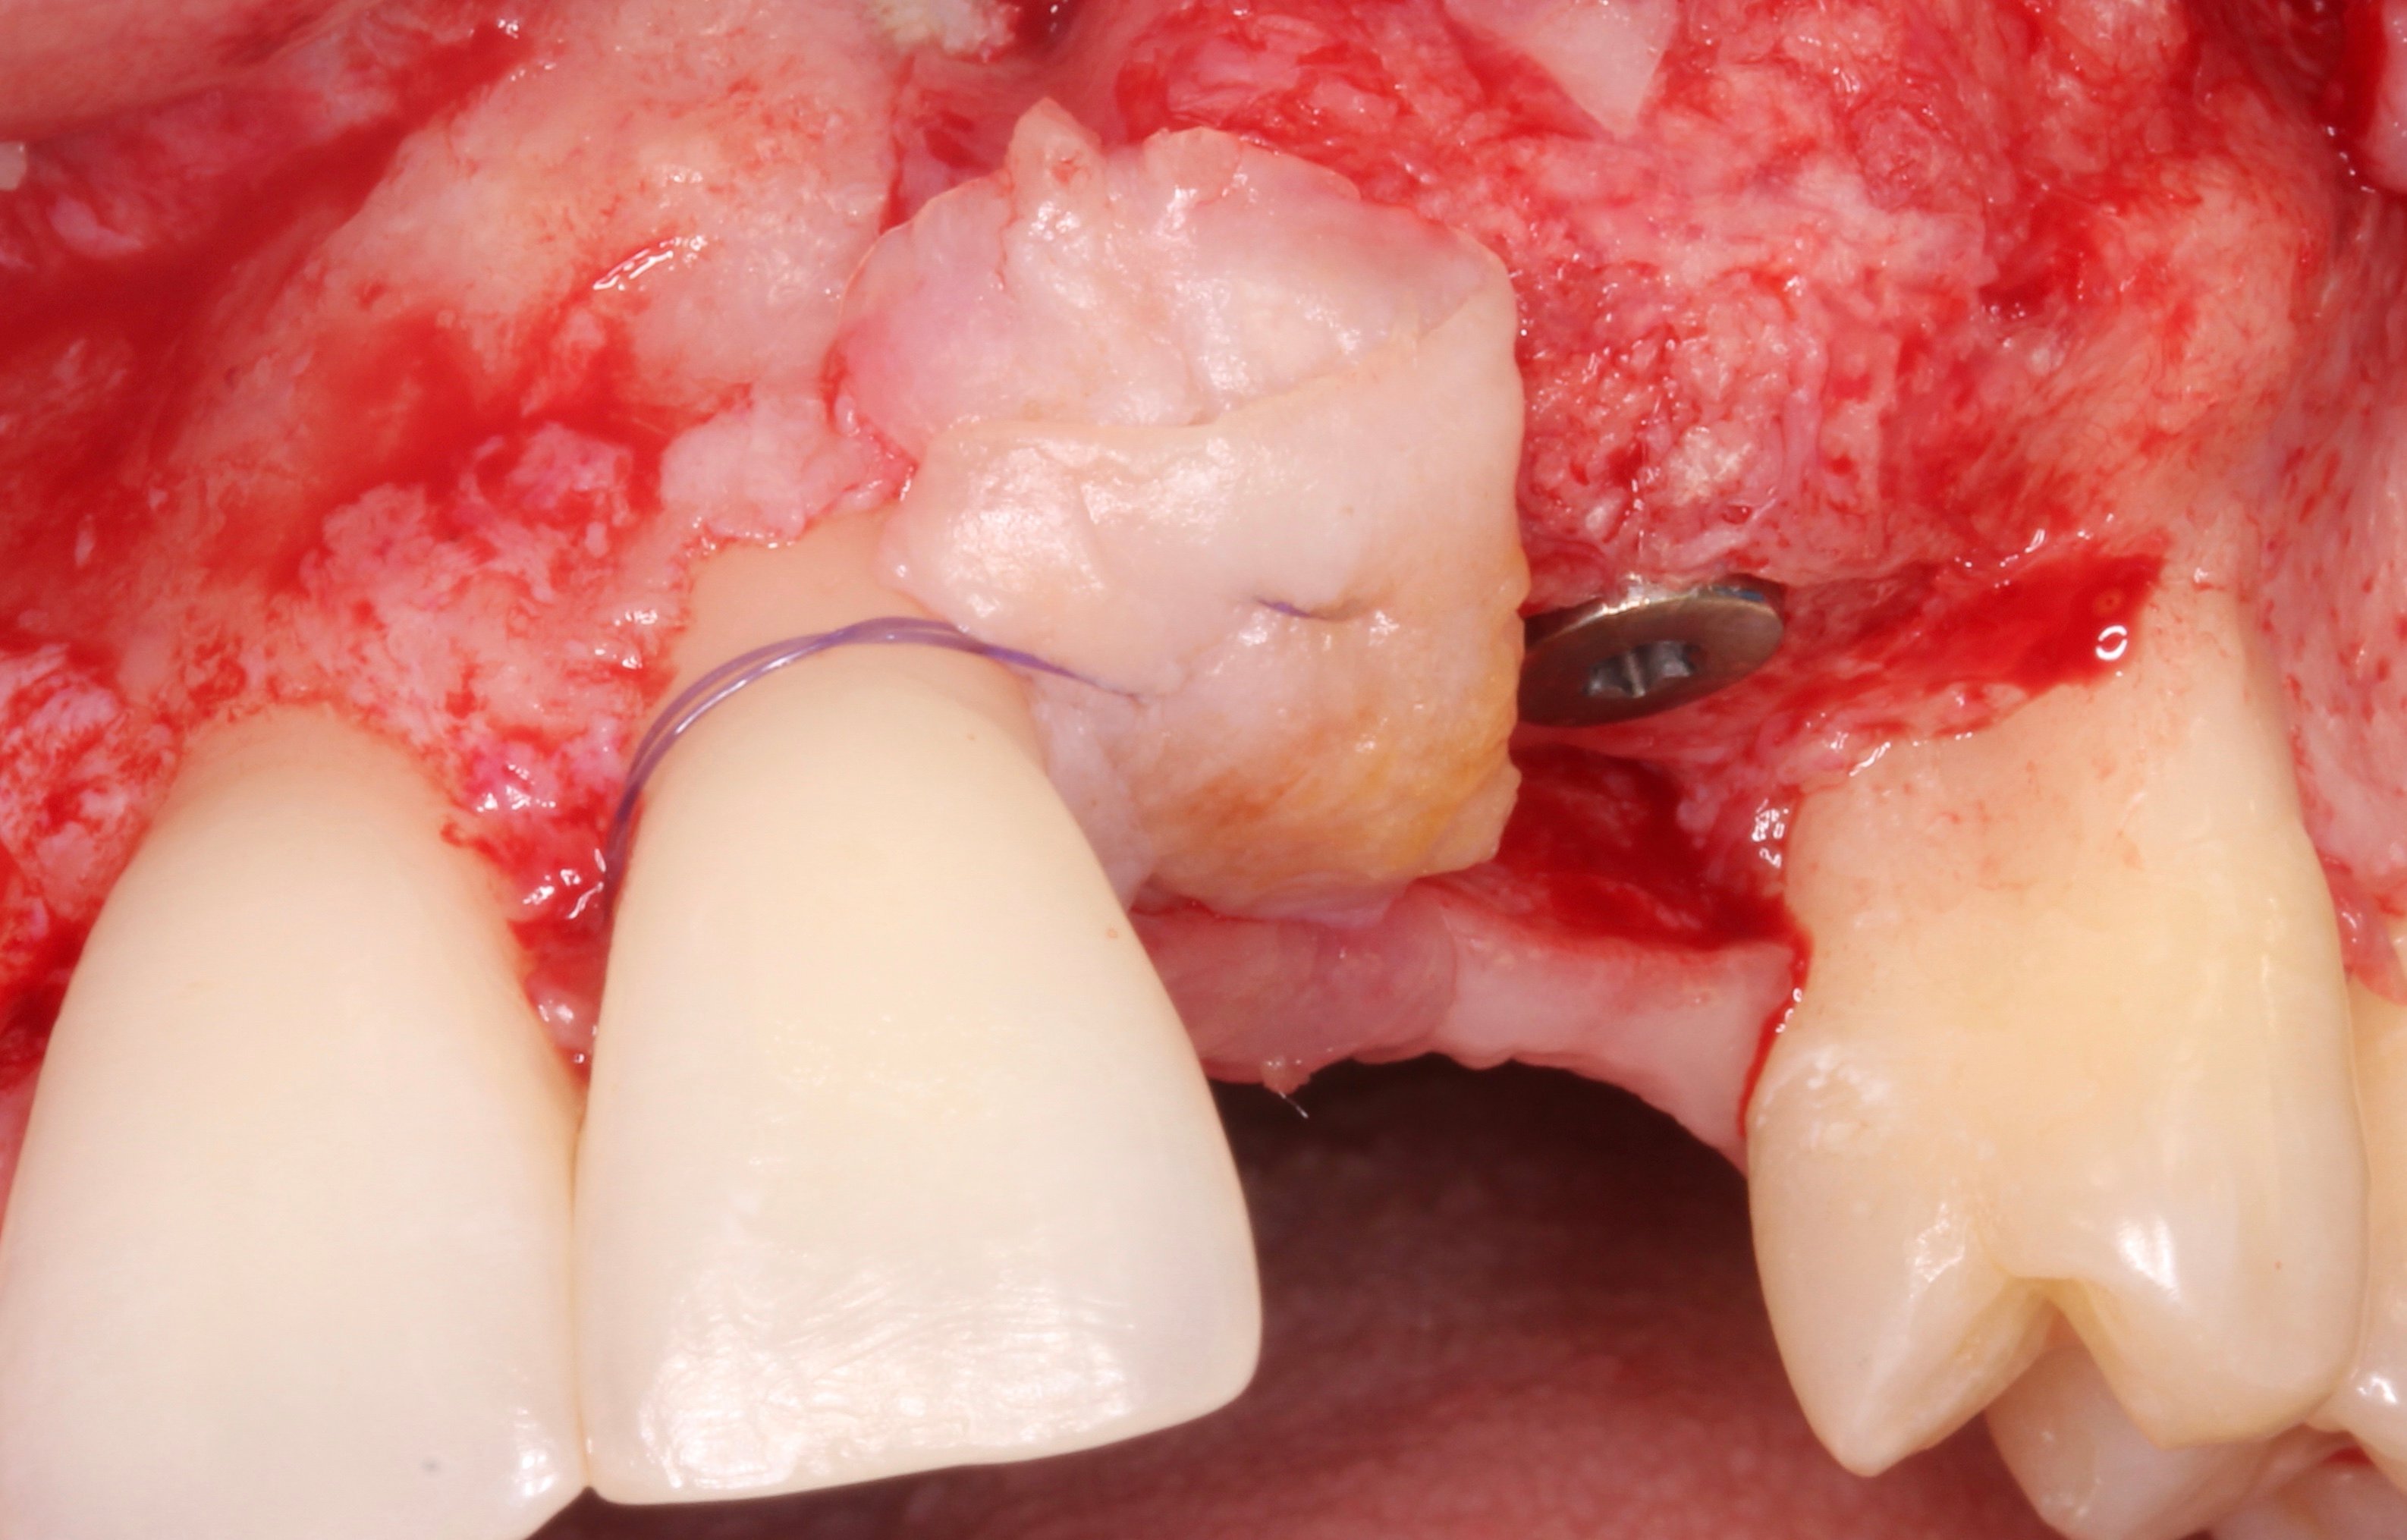

- 3 months later: (which turned out to be 2 years later because the patients was treated and failed elsewhere): 3D guided bone regeneration using 100% autogenous bone and a PTFE, Ti-reinforced NeoGen® membrane which was fixed by Neoss Tacks.

Step by step

Figure 2.